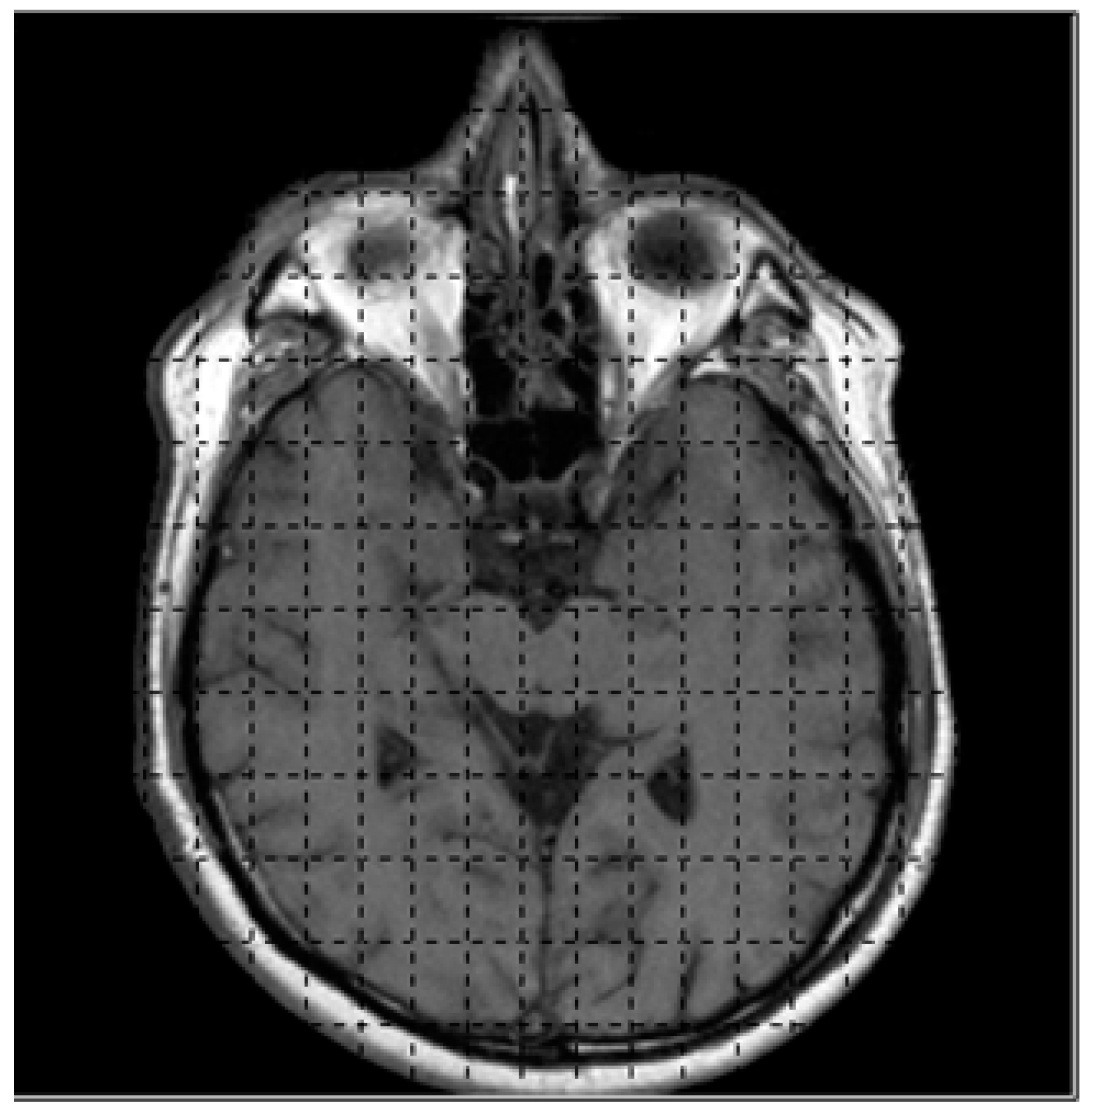

The first step for obtaining the intensity value of medical images begins with reading the coordinates and values then store them in the data structure of the system, e.g., the binary image with dimension of 256 × 256 will be read and kept in the array. The input array will be manipulated for marching cubes and histogram pyramids. Figure 7 shows the binary image and grid structure used for dividing image into 128 × 128 segments.

Figure 7.

The input image with 128 × 128 segments.